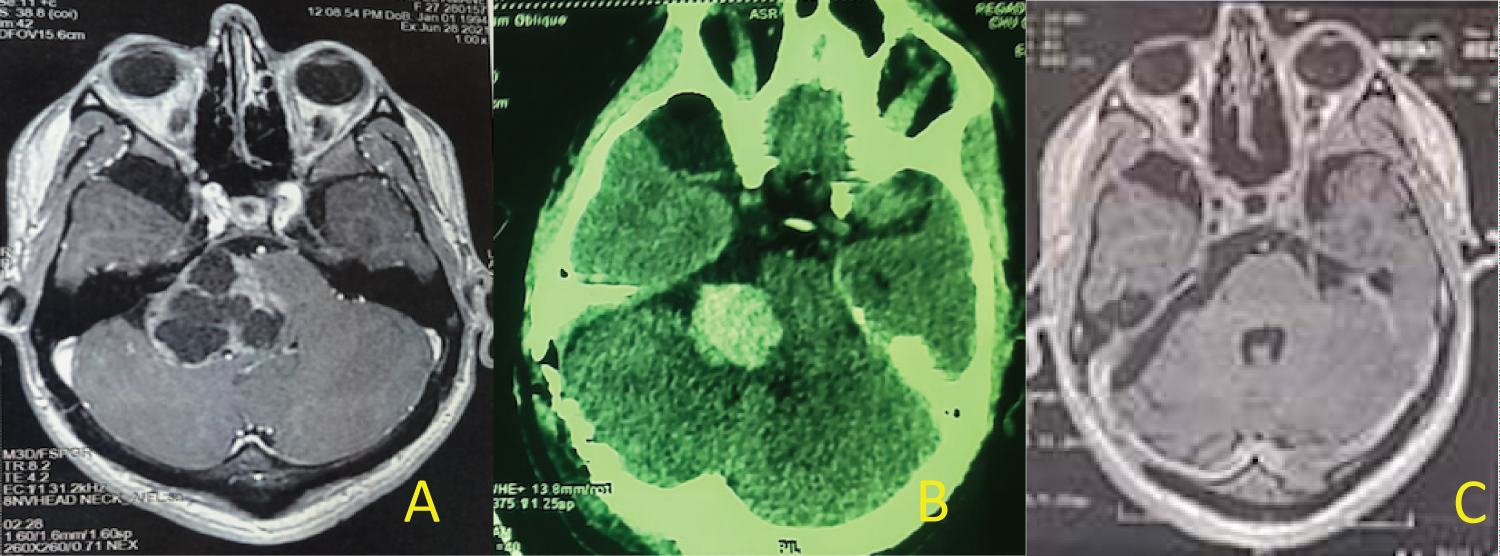

- In the first situation the cystic wall of the VS is immediately visible and facilitates access to the CPA: 01 case (Figure 1).

Figure 1: (A) MRI of giant cystic vestibular schwannoma; (B) The cystic wall of the VS is immediately visible; (C) Solid part of cystic VS; (D) Anatomic preservation of facial nerve and a thin layer of tumor was left over the facial nerve. View Figure 1

- In the second situation, to expose the tumor the cerebellum must be retracted with a narrow brain retractor and with a fine bayonet forceps the cerebellomedullary cistern was opened. The drainage of cerebro- spinal fluid (CSF) eased the cerebellum retraction: 11 cases (Figure 2).

Figure 2: (A) MRI of giant cystic VS type B (PC); (B) Evidence of the cyst wall after cerebellum retraction; (C) anatomic preservation of facial and cochlear nerve and a thin layer of tumor was left over the facial nerve; (D) postoperative MRI showing near total resection of cystic VS. View Figure 2

In cystic VS type A (PC) [3], identification and dissection of the facial nerve is less difficult in 03 cases (Figure 3). In type B (PC) the cyst is peripheral with a thin and fragile wall, making the establishment of a dissection plane more difficult (Figure 1 and Figure 2). When the facial nerve strongly adheres to the tumor, a thin layer of the tumor is left in place to preserve its integrity and especially its function 03 cases. In 2 cases the facial nerve was identified at the level of the brainstem but its identification on the wall of the cyst was impossible. For these 2 patients we proposed a facio-hypoglossal anastomosis.

Figure 3: (A) MRI of giant cyst VS; (B) CT scan: Postoperative hematoma; (C) Postoperative MRI with great total tumor resection. View Figure 3